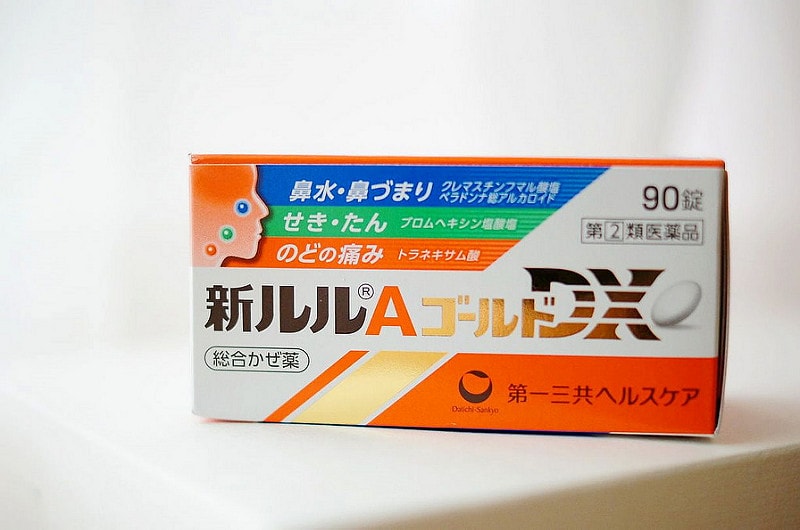

新露露A錠,這是日本綜合感冒藥

我個人覺得必買耶,雖然本人很強壯不怎麼感冒

我是買來給很容易破並的老逼吃的XD

還記得有年來日本老逼因為室內室外溫差大突然感冒

還發燒到不能跟我們的行程只能待在飯店

那天我跟小妖去逛藥妝店就問店員有什麼推薦給病人吃的藥

就買了露露A回去,老逼吃了病狀好很多還退燒

從此之後每次來日本就必買!!有點感冒症狀之前吃也很OK